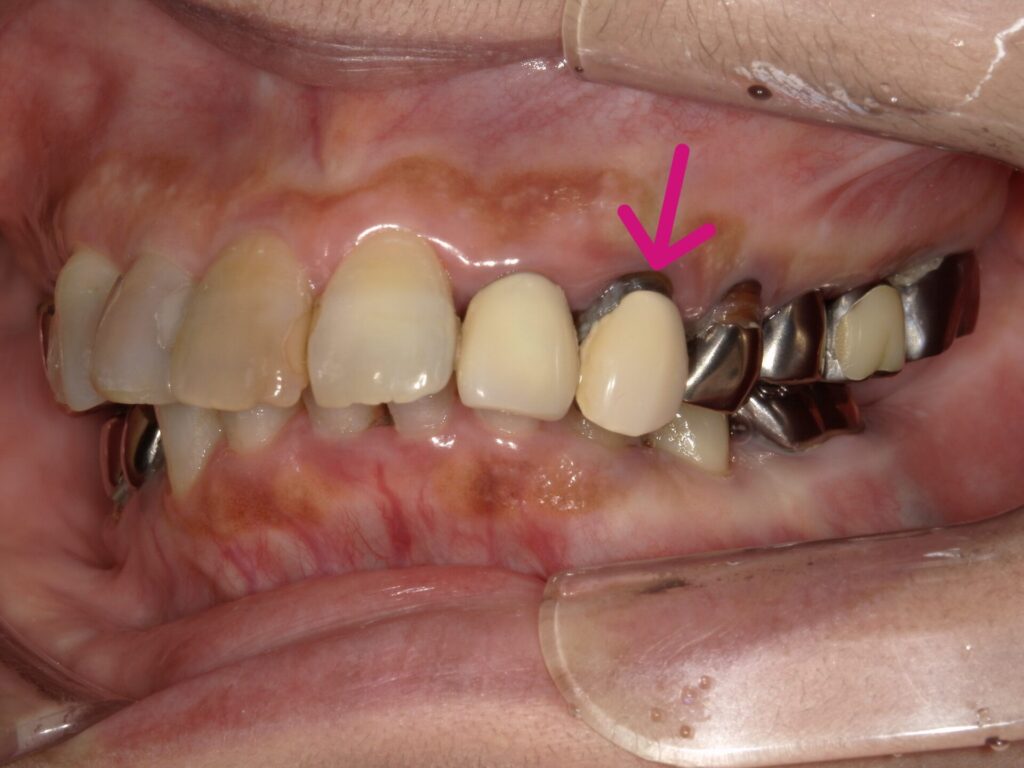

【初診時の口腔内】

左上3歯根破折のため抜歯。

抜歯と同時にインプラント埋入。その日のうちに仮歯まで装着します。切開縫合を行わないため腫脹、痛みの少ない患者さんにやさしい術式になります。

左上3歯根破折。右下56は当院にてインプラント埋入

抜歯と同時にインプラント埋入。サージカルガイドを使用することにより正確な位置に埋入可能